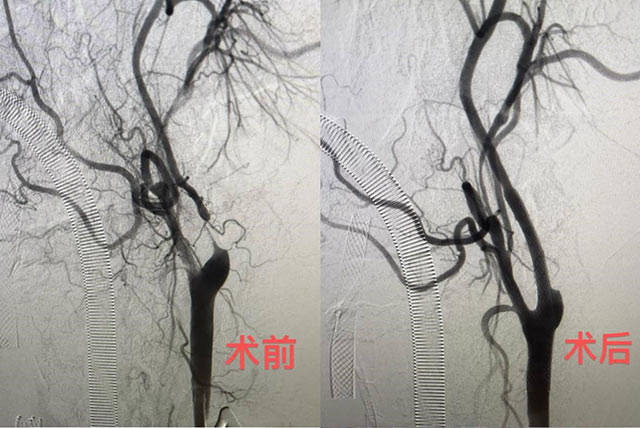

近日,备受头痛、耳鸣折磨的张伯(化名)被查出颈动脉重度狭窄。广东省人民医院(以下简称“省医”)神经外科团队为他实施了颈动脉狭窄治疗的全新术式——经颈动脉血运重建术(TCAR)。术后,张伯状况良好,目前已康复出院。

“经颈动脉血运重建术则是一种全新的、结合上述两种传统治疗方法优势的颈动脉介入治疗方法,将颈动脉显露与血流逆转相结合,最大程度减少栓塞发生的可能性。”陈光忠进一步解释,以颈动脉支架成形术为例,术中放球囊扩张血管时可能导致斑块碎片脱落,如果保护伞未能兜住脱落的血栓,它们进入脑部血管里就可能引发脑梗死。

而新术式采用“血流逆向”的理念,在患者体外接一条从颈动脉接到股静脉的人工血管,体外血管安装血流逆向保护装置,该装置有着特别密的保护网,能兜住绝大部分脱落的血栓,从而破解血栓脱落流到脑血管的问题。

经颈动脉血运重建术在华南地区成功开展,让颈动脉狭窄患者有了更多的治疗选择。“经颈动脉血运重建术具有微创、避开颅神经损伤、血流逆向保护等优势,30天围手术期总卒中发生率低至1.4%(传统术式的发生率约为5%),让颈动脉狭窄的治疗更加安全有效。”陈光忠介绍,新术式特别适用于高龄、心肺功能差、高位病变、术后再狭窄、血管路径迂曲等颈动脉狭窄患者。